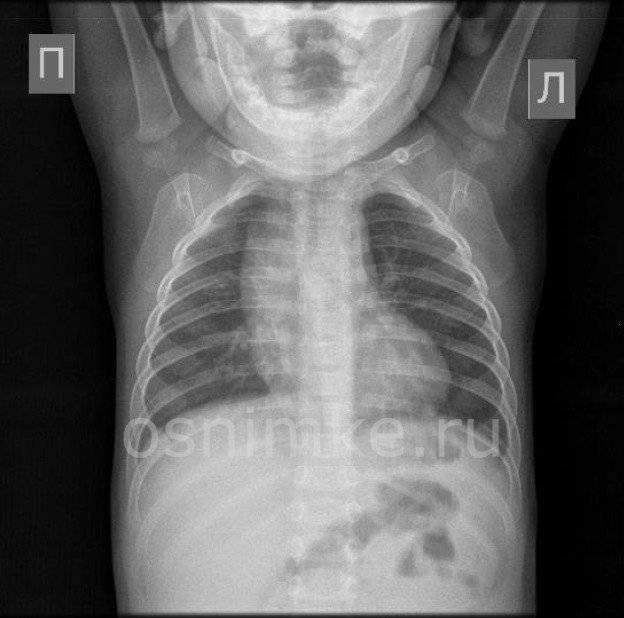

Снимок грудной клетки здорового ребенка: примеры и диагностика